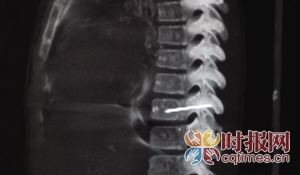

医生给小患者拍的片子

一根5厘米长的绣花针竟然在12岁男孩胸壁内藏了4年!近日,重医附属儿童医院胸心外科,医生通过微创手术从一名12岁男孩胸部取出一根长约5厘米的绣花针,取出的绣花针已经锈迹斑斑。昨日,重庆时报记者了解到,手术后男孩已经能下床进行活动了。

男孩名叫小照,12岁,家住永川。今年5月,小照因感冒咳嗽不止到当地医院拍胸片检查,医生惊讶地发现小照左侧胸部有异物。7月5日,小照放假后,父亲何先生便带着小照来到了儿童医院进行全面检查,发现小照左侧胸壁有一根绣花针。

“绣花针的位置离心脏仅有三四厘米,而针尖距主动脉更只有短短1厘米,针在身体内很有可能会在移动时戳破主动脉,引起大出血。”重医附属儿童医院胸心外科副主任医师李勇刚说,生锈的针在体内如果引起感染,也可能发生破伤风,必须尽快取出。

7月9日,医生对小照进行了胸壁异物取出术,取出了这根绣花针。李勇刚说,绣花针在体内已生锈。李勇刚诊断,孩子出现发热情况,可能就是因这枚绣花针引起的。